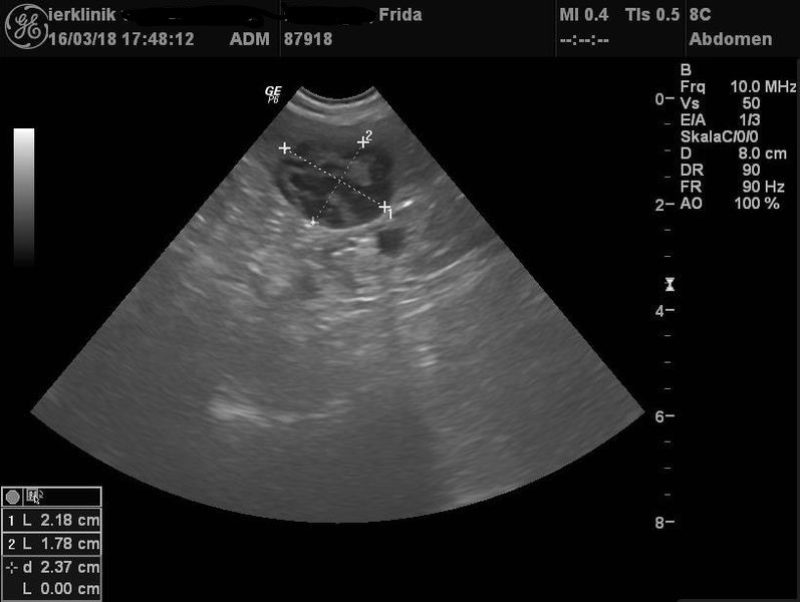

Anfang 2017 ging es Frida dann richtig schlecht. Sie wurde in einer Klinik zur Ultraschalluntersuchung vorgestellt. Das Ergebnis war niederschmetternd: Tumoren an Leber und Milz. Und dies auch noch in einem Umfang, dass die Klinik gleich zur Euthanasie geraten hat. Zu Fridas Glück wollten ihre Besitzer dies aber nicht und haben sich mit ihrem Haustierarzt, Dr. Schabel, in Verbindung gesetzt.

Der intensive Aufwand hat sich bisher mehr als gelohnt: Frida ist fit wie ein Turnschuh. Die sonographische Kontrolluntersuchung drei Monate nach Diagnosestellung zeigten auch eine Verkleinerung des Milztumors um rund ein Viertel. Wir sind alle glücklich, dass unser Sonnenscheinchen nun schon seit zwei Jahren nach Euthanasieempfehlung ein glückliches und gutes Hundeleben führt.